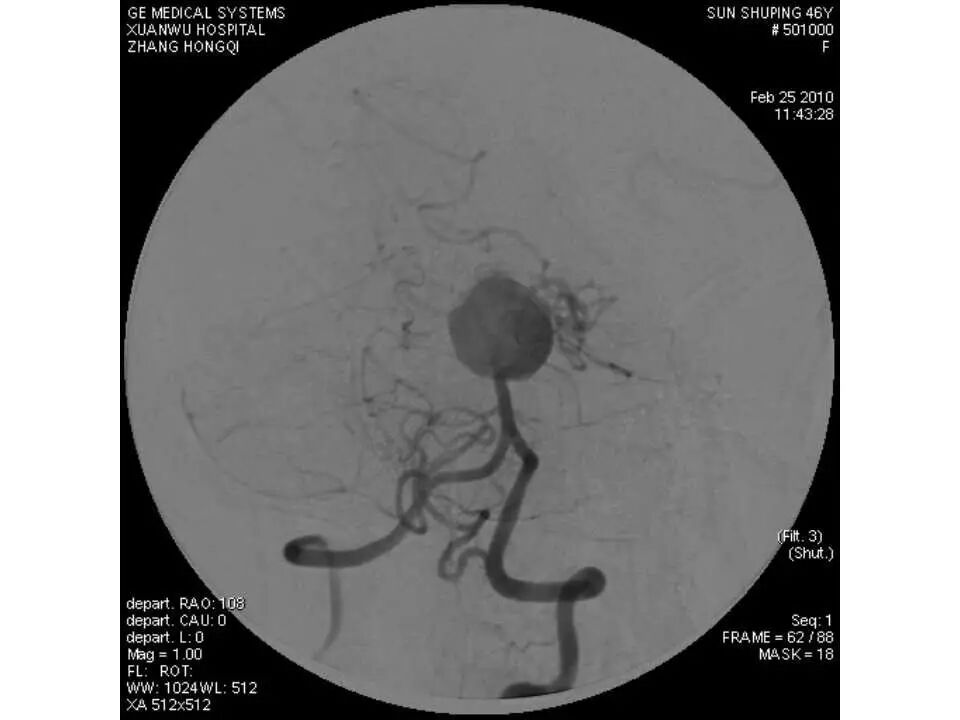

今天为大家分享的是“强生医疗CNV-神经介入专栏”第十五期,由首都医科大学宣武医院何川教授带来的“颅内动脉瘤介入治疗”精彩讲课视频及PPT,欢迎观看、阅读。文章仅代表作者个人观点,如有不同见解,欢迎同道斧正!